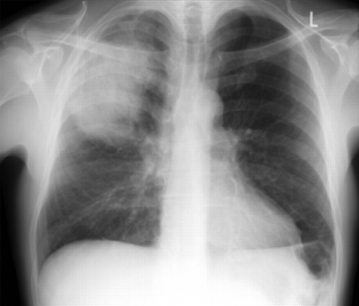

Radiografía de tórax posterior-anterior que muestra consolidación del lóbulo superior derecho en un paciente con neumonía adquirida en la comunidad

Durrington HJ, et al. Recent changes in the management of community acquired pneumonia in adults. BMJ 2008;336:1429.